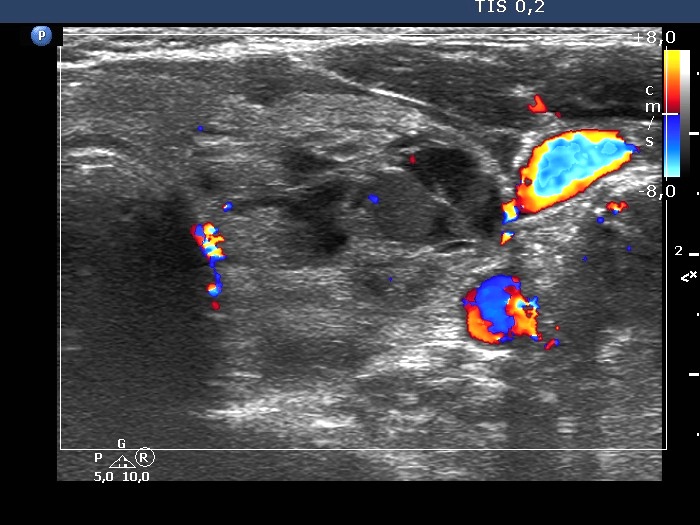

Left lobe, transverse scan, color Doppler mode. The vascularization is not specific.